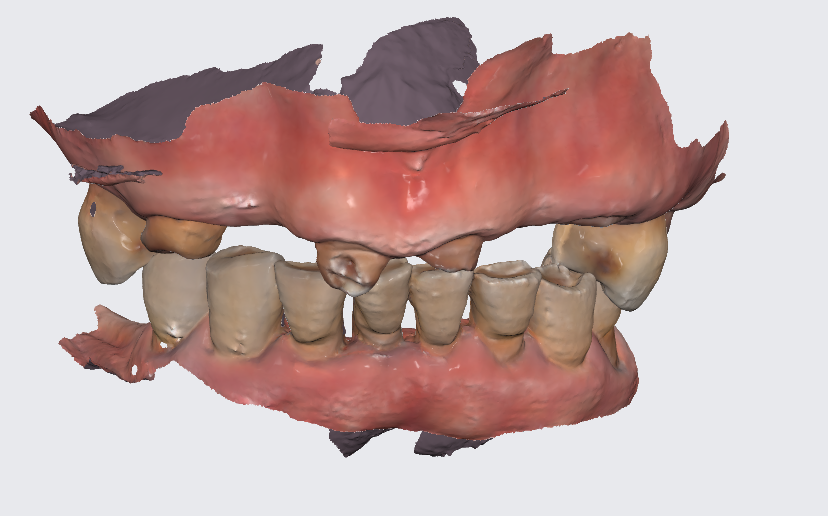

전반적인 어금니 상실로 내원해주신 환자분입니다.

딱 보기에도 제 기능을 하는 어금니가

몇개 없어보입니다.

23.08.17

큰 어금니는 다 뽑히고

작은 어금니 1지점씩만 닿고 있습니다.

디지털 기술이 있었기에

하루만에 전체 임플란트가 가능했는데요~